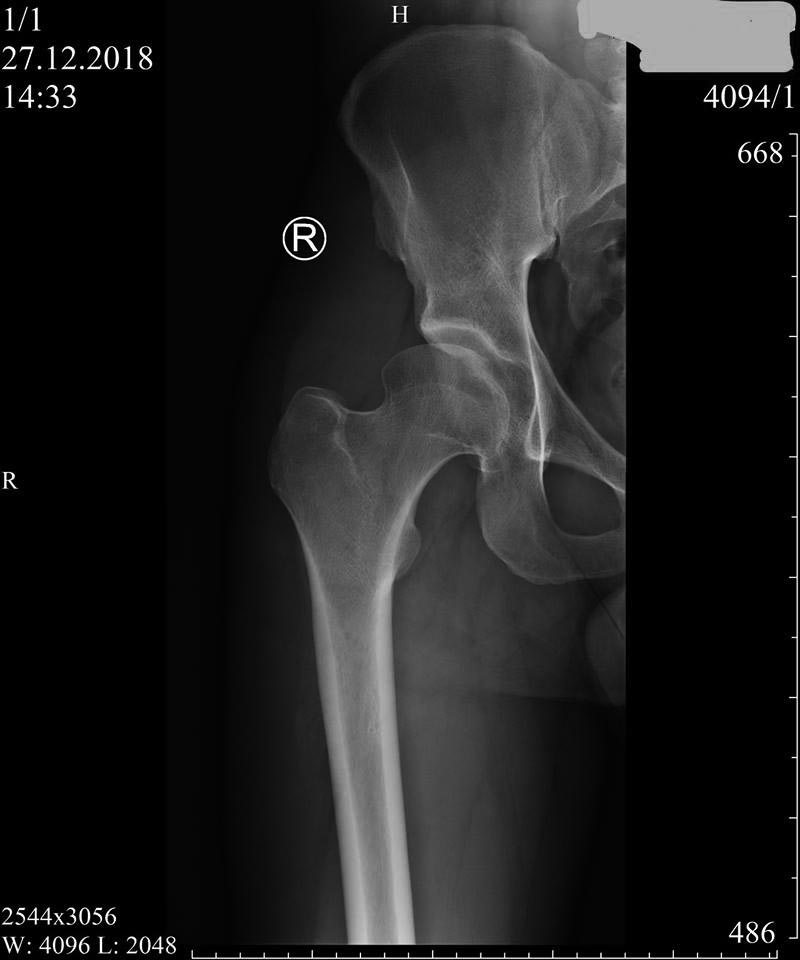

Пациент 27 лет: с 14-ти - "щёлканье" в тазобедренных суставах... Последние полгода - боль (особенно после вставания из положения сидя), которая устраняется "встряхиванием" ноги (правой) со "щелчком"...

У Вашего пациента, скорее всего банальная дисплазия тазобедренного сустава. Не исключается и феморо-ацетабулярный импинджмент кулачкового типа ( cam FAI). Возможная причина щелчка - лабральный разрыв (?)

На представленном снимке (frog lateral) хорошо можно увидеть шейку и головку, но для данной патологии требуется false profile view! Для удобства приложил некоторые укладки: false profile и снимок с нормальными параметрами сустава (синими указаны центр край угол). Здесь имеется измененная и деформированная диспластическая форма головки, где огромный размер, выходя за пределы вертлужной впадины, создает иллюзию подвывиха. Очень узкая нагрузочная площадь и почти негативный (center-edge angle of Wiberg), потому что вертикаль (зеленая) от центра головки проходит с латеральной стороны. Контур передней стенки (синий) показывает что покрывает головку мало, а задняя стенка (красная) больших размеров доказывает что сустав развернут кпереди. Возможно за счет укладки, на рентгене слева шейка вроде короткая.

Для определения диагноза, кроме рентген снимков, необходим клинический осмотр. При таком суставе внутренняя ротация конечности увеличивается, а наружная ротация лимитирована. Чрезмерная флексия и ротация покажет симптомы повреждения лабрального хряща.

В данном случае имеется возможность сохранить сустав, рекомендуется остеотомия таза, которая увеличит нагружаемую поверхность и улучшит переднее покрытие. Тройная остеотомия имеет свои отрицательные стороны, например, из-за вовлечения задней колонны затягивается восстановление и бывают проблемы в акушерской практике. PAO (периацетабулярная остеотомия) таза позволяет исправить все деформации через один передний доступ.